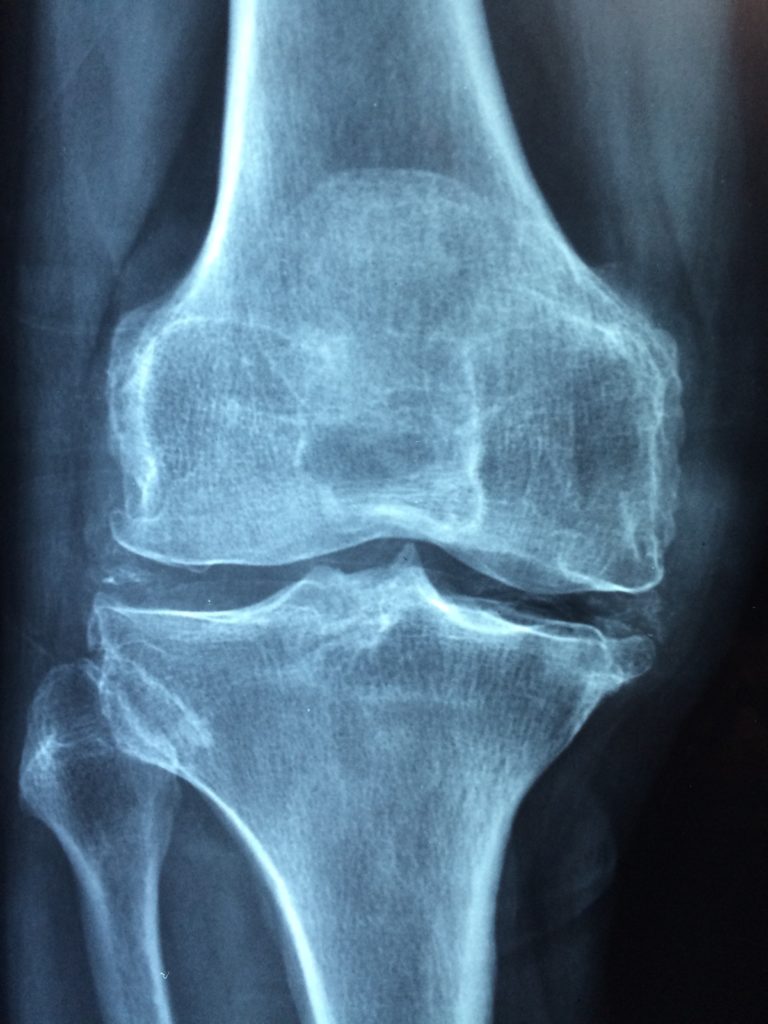

Pathologie systémique de l’os, l’ostéoporose ne fait pas partie des maladies féminines. Elle touche cependant 2 à 3 fois plus souvent les femmes que les hommes. Après 65 ans, elle concerne près de 39 % des femmes et 70 % après 80 ans. Cependant, le passage à la ménopause semble le principal facteur de l’ostéoporose chez la femme. Elle résulte d’une altération de la microarchitecture des os et d’une diminution de la masse osseuse. Automatiquement, les os deviennent plus fragiles et le risque de fracture augmente considérablement.